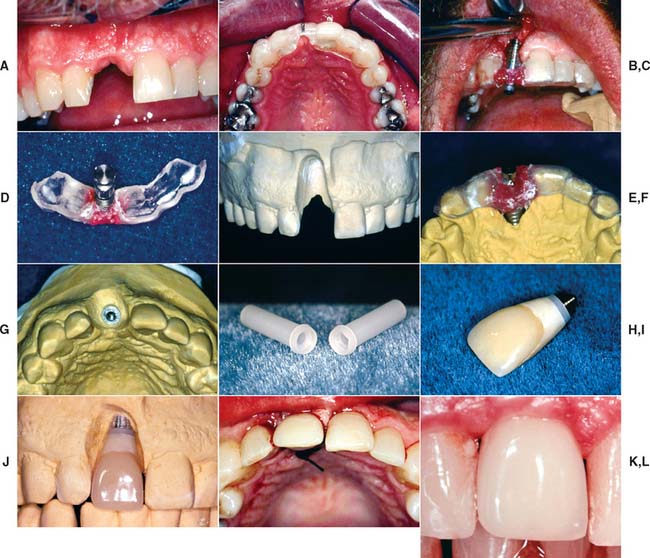

Several systems have been developed to comply with these demands. Common indications include congenitally missing maxillary lateral incisors (Fig. 13-42) and teeth in which endodontic treatment was unsuccessful (Fig. 13-43). Screw loosening has most commonly been associated with the terminally positioned single molar implant crown (Fig. 13-44).

Fig. 13-42 A, Patient with congenitally missing maxillary lateral incisor. B, Placement of dental implant through the use of a surgical template. C, Final soft tissue contours. D, Impression post projecting from definitive cast. E and F, Final restoration. G and H, Single tooth implant crown replacing the maxillary lateral incisor.